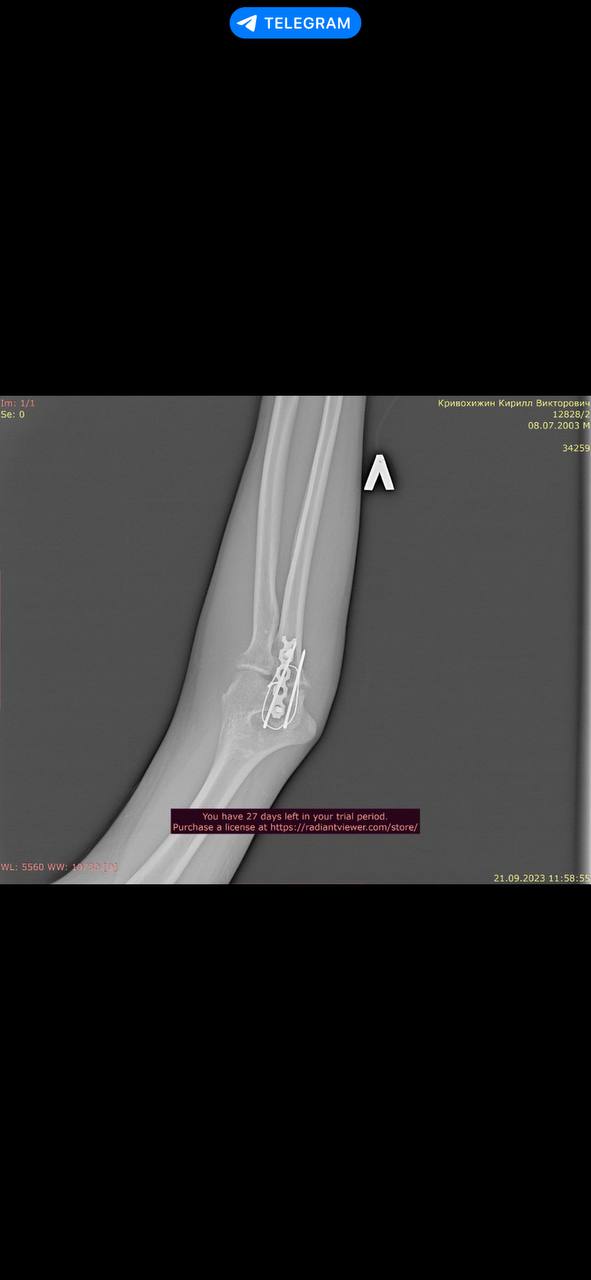

2 года назад получил тяжелые травмы, в результате чего мне установили металлоконструкции в плече и локте левой руки и в луче правой руки.

Снимки трех металлоконструкций прилагаю. Их не удалял и удалять не планирую.